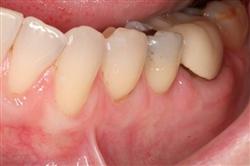

Cosmetic Soft Tissue Grafting can add a new youthful appearance to your smile. In your initial consultation with Dr. Hoidal, he will thoroughly explain what can be achieved in your particular case.